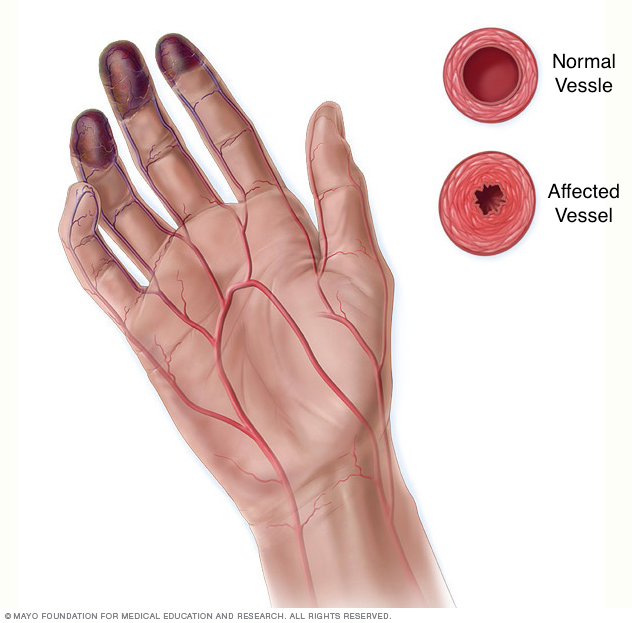

This page is dedicated to covering how the condition Buerger disease (thromboangiitis obliterans) will appear on different types of radiological imaging studies. This condition is a medium/small vessel arteritis that predominantly is seen in young male smokers. It can cause obstruction of the involved vessels resulting in ischemia.

- Corkscrew/collateral vessels: while not pathognomonic, these are characteristic of this condition.

- Arterial occlusion